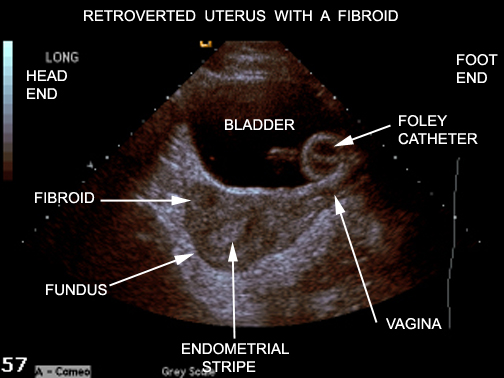

Image17A.jpg Image17A.jpg From lumen.luc.edu

Image17A.jpg Source: lumen.luc.edu